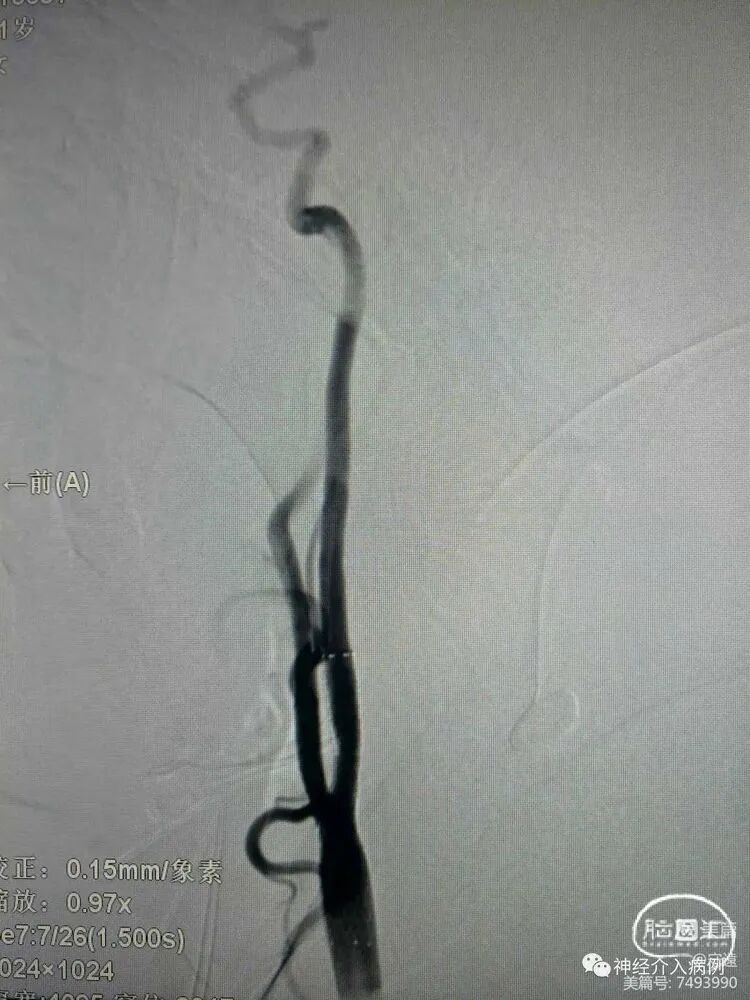

股动脉鞘拔除按压出现迷走反射低血压。

手术顺利,生命体征平稳正常。于术后缓慢拔出右侧股动脉鞘管,按压股动脉穿刺部位,同时察看反应,突然出现呼叫无应答,面色苍白,测血压72/46mmHg,脉搏43次/分。立即使病人取平卧位,头偏向一侧,防止呕吐物误吸,立即从预先建立静脉通道,扩充血容量,维持有效循环,同时给予吸氧,因患者心率、血压下降,急给予“阿托品注射液1mg静脉推注及多巴胺注射液10mg静脉推注”,后患者意识逐渐恢复,测血压115/65mmHg,脉搏68次/分,同时持续给予“多巴胺注射液180mg+0.9%氯化钠注射液32mL”持续泵入(5-10ug/Kg/分钟),依据血压变化,调整泵速,直至血压稳定(>90/60mmHg),同时积极安慰患者,消除其焦虑心理。患者于术后安全出院。